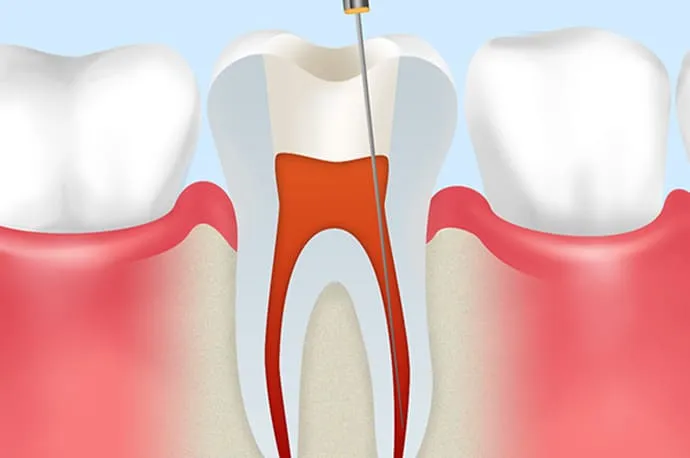

虫歯が重度に進行すると、虫歯菌が歯の神経まで感染し、歯の内部にある神経を取り除く必要が出てくることがあります。

根管治療とは、文字通り「歯の神経が入っている根の管(根管)」に対して行う治療です。 もし根管治療を行わずに放置してしまうと、細菌が歯の根の先にたまり、やがて根の先が化膿してしまいます。その結果、強い痛みが出たり、歯ぐきや頬が腫れたりすることもあります。

①抜髄

まだ死んでいない歯の神経を取り除く処置を抜髄といいます。虫歯や歯の破折が原因で細菌が歯の神経まで到達し、炎症を起こしている状態(歯髄炎)がこれにあたります。

原因を取り除くことで神経が回復する場合もありますが、炎症の程度によっては、早急に神経を取る必要があるケースもあります。

まだ細菌感染が成立していない段階で行う治療のため、治療の成功率は約90%とされています。

根管口を探す

歯の内部にある神経の部屋(髄室)へアプローチします。歯や患者さまによって神経の入っている根管の数は異なるため、それぞれの入り口(根管口)を慎重に探し出します。